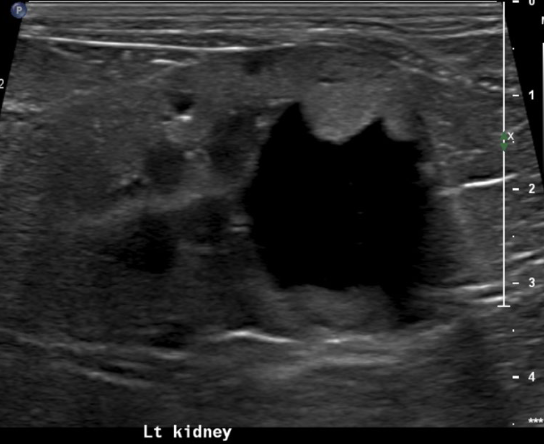

what is going on with this kidney

mass - cystic carcinoma

hypo/iso/hyperechoic ill defined mass ± cysts and mineralization